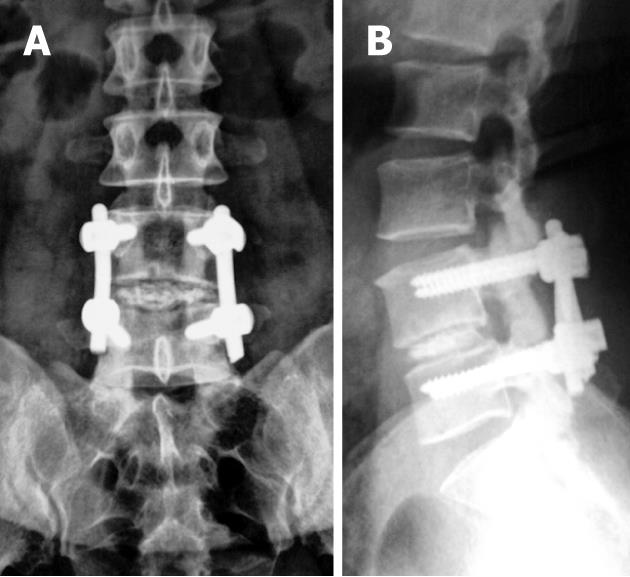

arthrodesis

surgical immobilization by fusion to adjacent vertebra

spinal fusion

using rods, plates, & screws to stabilize vertebra